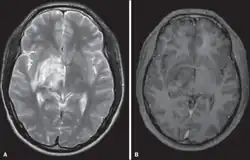

| Diagnostic method | Brain/Spine magnetic resonance imaging (MRI) [2] |